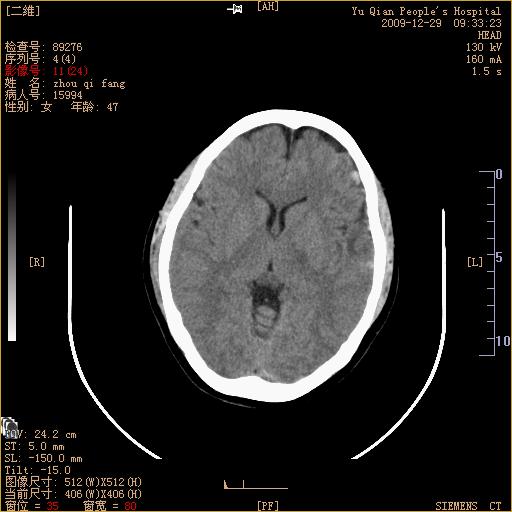

头部外伤后1天   请看看左侧丘脑外侧原是否为小血肿?(两天表现大致相仿。)谢谢

左颞叶前外部见片状挫裂伤,左丘脑小血肿;颅板下见多发小片状血肿影,两侧额部见少量蛛网膜下腔出血,

考虑:出血 最后一幅周围还是有水肿的

建议mri  ct薄层扫描检查对鉴别诊断会有帮助的

不好定。同时左侧裂池形态异常,左侧豆状核点状高密度,第四幅右额叶稍高密度影,最后一幅左额叶颅骨内板下方小片状高密度影。复查。